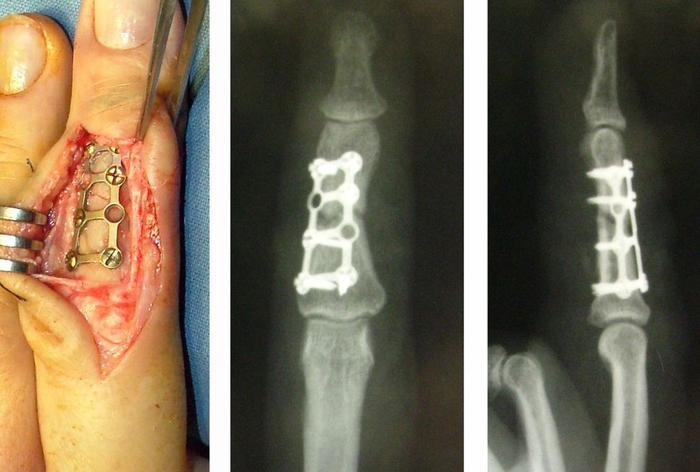

При переломах со смещением отломки обычно фиксируют – возможные способы: фиксация спицами через проколы кожи (спицы остаются на поверхности кожи), использование пластин или винтов через разрез. Начинать разрабатывать движения в суставах пальца можно через несколько дней после операции.

При переломах основания или головки фаланги фиксация обычно проводится спицами или винтами, в случае переломов диафиза – с использованием винтов или пластин. При многооскольчатых переломах может быть установлен внешний фиксатор.

Остеосинтез с пластиной и винтами:

Во время операции обеспечивается доступ к месту перелома, выполняется сопоставление отломков и их фиксация с помощью пластин и винтов. Швы закрываются, накладывается стерильная повязка, а перевязки производятся через день. Швы снимаются на 12-14 день.

Плюсы данного метода: полное восстановление анатомии фаланги; возможность ранней реабилитации суставов; гипсовая повязка используется всего на 2 недели.

Минус: как и после любой операции, остаётся небольшой рубец.